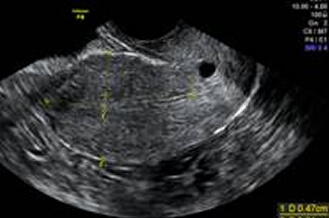

陰道超音波檢查

子宮肌瘤、卵巢巧克力囊腫、子宮內膜厚度、卵巢基礎濾泡數量…等,都可能影響受孕,這些資訊可以藉由陰道超音波檢查而得知。

超音波探頭伸入陰道後,可以縮短探頭與子宮和卵巢的距離,看到子宮和卵巢更多的細節。檢查約2~3分鐘內可完成。

正常子宮

正常卵巢

子宮肌瘤

卵巢巧克力囊腫